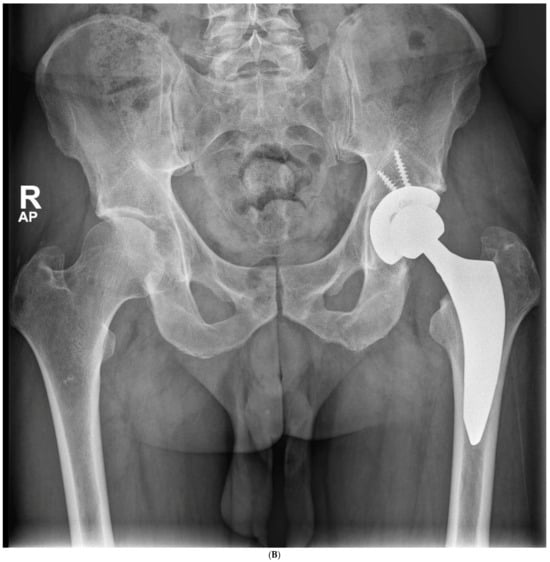

The average cup inclination and anteversion were 43° ± 3° (range, 38–50°) and 10° (range, 0–15°), respectively, in the SFS group, compared with 44° ± 5° (range, 37–50°) and 5° (range, 3–15°) in the CSS group. All acetabular components were positioned within Lewinnek’s safe zone. No radiolucent lines, cup migration, or broken screws were observed in either group throughout the follow-up period. Radiographic signs of osseointegration were present in all implants, with at least three of Moore’s criteria met in every SFS case (Figure 3A–C), indicating complete osseointegration. Similar findings were noted in the CSS group (Figure 4A–C). No femoral radiolucency or periprosthetic osteolysis was detected at any scheduled follow-up. Stem subsidence of approximately 3 mm was observed at the 3-month follow-up in two hips in the SFS group and three hips in the CSS group; however, these cases were not associated with clinical symptoms or functional impairment. No femoral stem loosening was identified during the follow-up period. A leg length discrepancy (LLD) of less than 1 cm was observed in three hips in the SFS group (average, 4 ± 3 mm) and in eight hips in the CSS group (average, 4 ± 5 mm). None of these discrepancies resulted in clinical or functional complaints, and no heterotopic ossification was identified in the radiographic evaluations (Table 4).

Figure 3.

(A) Preoperative anteroposterior X-ray. Left hip sustained a displaced femoral neck fracture. (B) Postoperative anteroposterior X-ray (SFS group). Both the short stem and acetabular cup appear well osseointegrated and stable at final follow-up. (C) Postoperative lateral X-ray (SFS group). The stem is osseointegrated and there is absence of radiolucent lines at bone-implant interface.